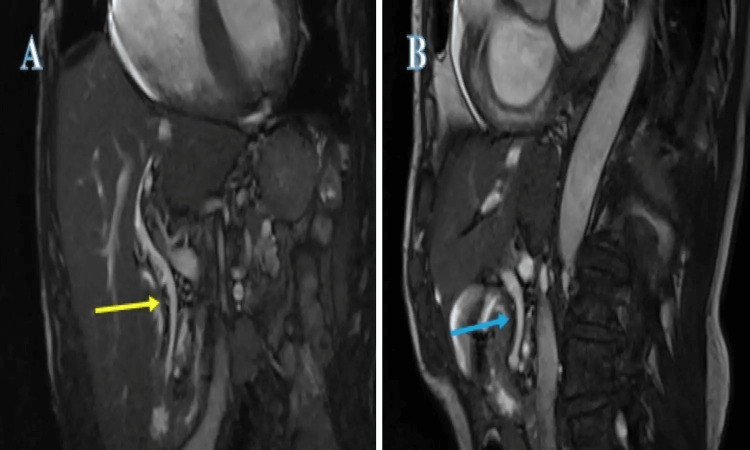

After discussing the risks and benefits, the patient elected to go with the alternative option of conservative management. It was explained that if he developed significant right upper quadrant pain, fever, or felt very unwell, he should seek urgent medical attention. In the interim, the general practitioner (GP; family doctor) was advised to start the patient on ursodeoxycholic acid 300 mg twice a day and to give the patient a backup prescription of co-amoxiclav 625 mg TDS for one week. The patient was advised to take the ursodeoxycholic acid for three months, the continuation of which was to be decided during his next clinic review. The backup prescription of co-amoxiclav was intended for when the patient felt slightly unwell or developed mild abdominal pain but felt well enough that he did not think presenting to the hospital was necessary. He was booked for a follow-up clinic review in six months’ time for clinical assessment and re-discussion of the options available with monthly interim LFT at the GP’s surgery (clinic). His LFTs were normalised and a repeat MRCP at the gastroenterology clinic review showed the disappearance of the CBD stones (Figure 3).